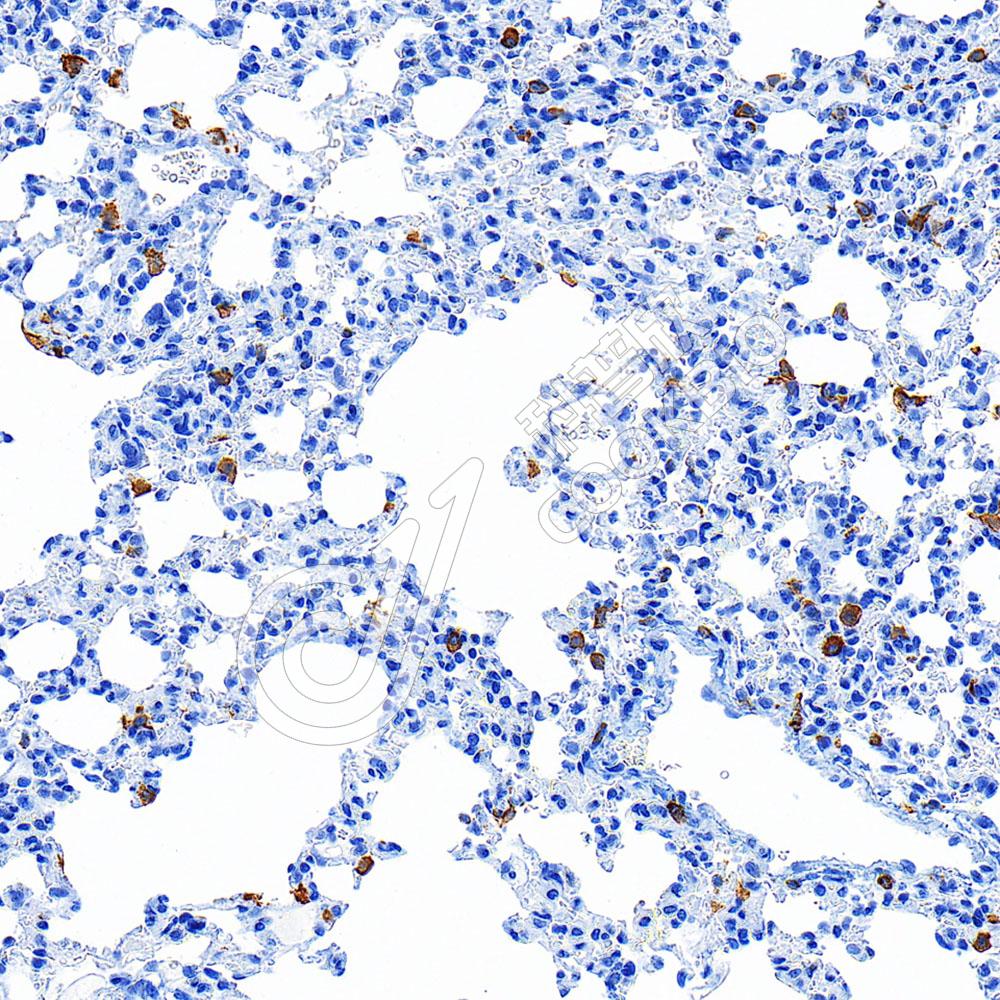

IHC检测CD32蛋白(货号 K1344499).

样品: 小鼠脾, 4%多聚甲醛 (货号KSG1101) 固定12-24小时.

抗原修复: 柠檬酸抗原修复液(干粉, pH 6.0) (KSG1201), 98℃, 20分钟.

—抗: 1: 600稀释, 4℃ 孵育过夜.

二抗: S-vision免疫组化多聚二抗(山羊抗兔),即用型 (货号KB3906), 室温孵育20分钟.